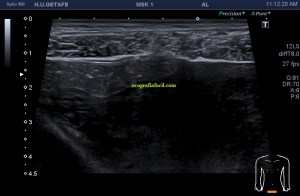

Estudiamos la región palmar del dedo en modo 2D, con una sonda de alta frecuencia, usando la máxima frecuencia de su rango dinámico, ajustando parámetros técnicos (pincha en los enlaces), como el foco, la frecuencia y la ganancia general, así como la profundidad y el rango dinámico para conseguir la mejor imagen posible, te lo muestro en la imagen 1.

1

En la imagen 1, tienes en un recuadro amarillo los datos de imagen que nos interesan y que te he contado en el párrafo superior y que te comento aquí:

Flecha azul: El Modo de trabajo de 2D, el más usado en ecografía clínica.

Flecha Blanca: Ganancia general, valor ajustable a cada paciente y que nos da el brillo de la imagen.

Flecha amarilla: Rango dinámico, valor que interviene en el contraste de la imagen.

Flecha rosa: Potencia de transmisión, la cantidad de energía a la que trabaja la sonda, es un porcentaje.

Recuadro rojo: Frecuencia usada, en este caso valor cualitativo, expresa frecuencia de resolución o máxima.

Recuadro azul: Profundidad utilizada, 2 centímetros, adecuada para una parte tan superficial.

Una vez revisadas las características técnicas de la imagen, pasamos a estudiar la ecoarquitectura. Mira: